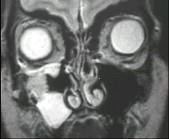

问题 女性,50岁,右鼻塞、脓涕3个月,CT、MRI检查如图所示,请选择正确的答案()

选项 A.右侧上颌窦黏液囊肿 B.右侧上颌窦粘膜下囊肿 C.右侧上颌窦积液 D.右侧上颌窦黏液腺瘤 E.右侧上颌窦腺样囊性癌

答案 E